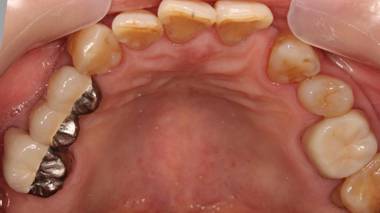

歯周病で抜歯せざるを得ず、インプラントを希望されたケース(使用インプラントはスプライン)

術前。すべての歯が歯周病の末期状態でブリッジ全体がうごいて噛めないとの訴え。右上の犬歯が腫れていました

固定式のブリッジが入っていましたが歯周病で動いています

下顎前歯部には歯石の沈着がみられます